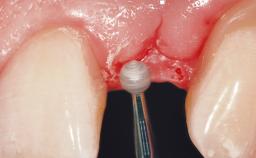

Immediate Placement of an Implant in a Maxillary Left Central Incisor Site

A 33-year-old female patient presented with an upper left central incisor that required extraction after a failed endodontic therapy. The tooth had been traumatized when the patient was a teenager and had undergone several endodontic treatments, including two apicectomy procedures. The patient was in good health and did not smoke. Clinical examination showed that the patient had a high lip line. In full smile, the gingival margins of the upper teeth were visible to the first molars. The gingival margins of central incisors 11 and 21 were only just showing. Examination of tooth 21 confirmed that the tooth was mobile and had hypererupted by 1 mm.

Lip Line No exposure of papillae Exposure of papillae Full exposure of mucosa margin

Provisional Implant-Supported Prosthesis Prosthodontic margin > 3 mm apical to mucosal margin Prosthodontic margin > 3 mm apical to mucosal margin